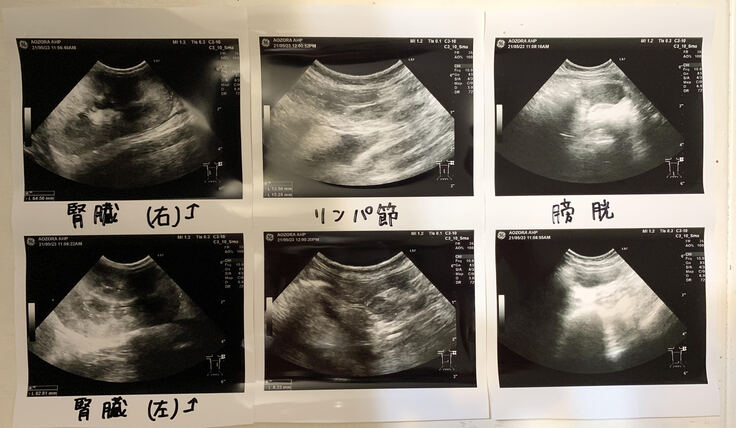

状況の共有、面談を行い血液検査、エコー検査を実施。

体温は37.6度まで下がりましたが、体重は3.6キログラムにまで減少しており(3日間で0.4キログラム、月内に1.0キログラムも減少)、黄斑もはっきりと見られるようになりました。

現時点ではFIPの可能性が非常に高いという診断でしたが、もしそうだった場合、非常に進行の早い恐ろしい病気である事を考慮し、すぐに治療薬の処方を開始する必要ありと判断。

脱水症状も深刻であったため、3日間の入院期間を設け、治療薬の投与以外に皮下点滴、静脈点滴等の治療を行い体調を改善させ体力を回復させる方針を取ることしました。

※3日前よりも、ほぼ全ての数値が悪化しています。

※腎臓とリンパ節が炎症によりなんと1.5倍も肥大。FIPの特徴でもあるそうです。